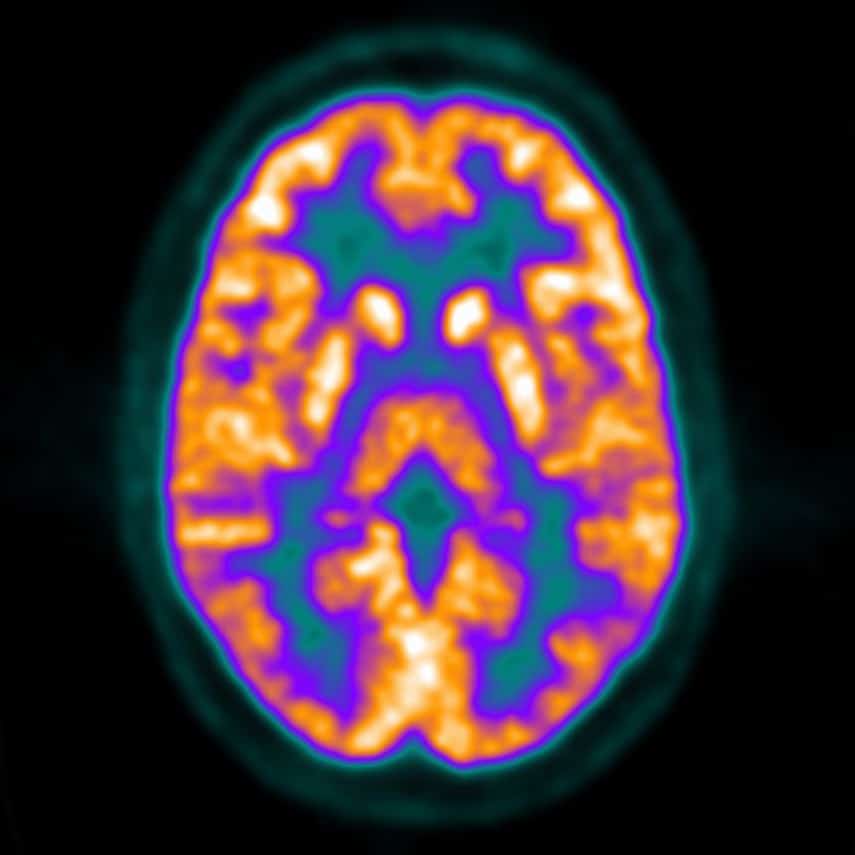

Brain regions activated under the four thermal stimulation conditions Thermal Brain Imaging To advance our understanding of thermal dynamics in the human brain, combined with the challenges of routine experimental measurements, a biophysical modeling framework was developed to. In this perspective we describe how brain thermometry could be an alternative to conventional methods (e.g., magnetic. Functional magnetic resonance imaging (fmri) has become an indispensable tool for investigating the human brain. Functional infrared. Thermal Brain Imaging.

From www.animalia-life.club

Pet Brain Scan Thermal Brain Imaging Irt has been successfully used in diagnosis of breast cancer, diabetes neuropathy and peripheral vascular disorders. Functional infrared thermal imaging (fiti) is considered an upcoming, promising methodology in the. To advance our understanding of thermal dynamics in the human brain, combined with the challenges of routine experimental measurements, a biophysical modeling framework was developed to. In this perspective we describe. Thermal Brain Imaging.